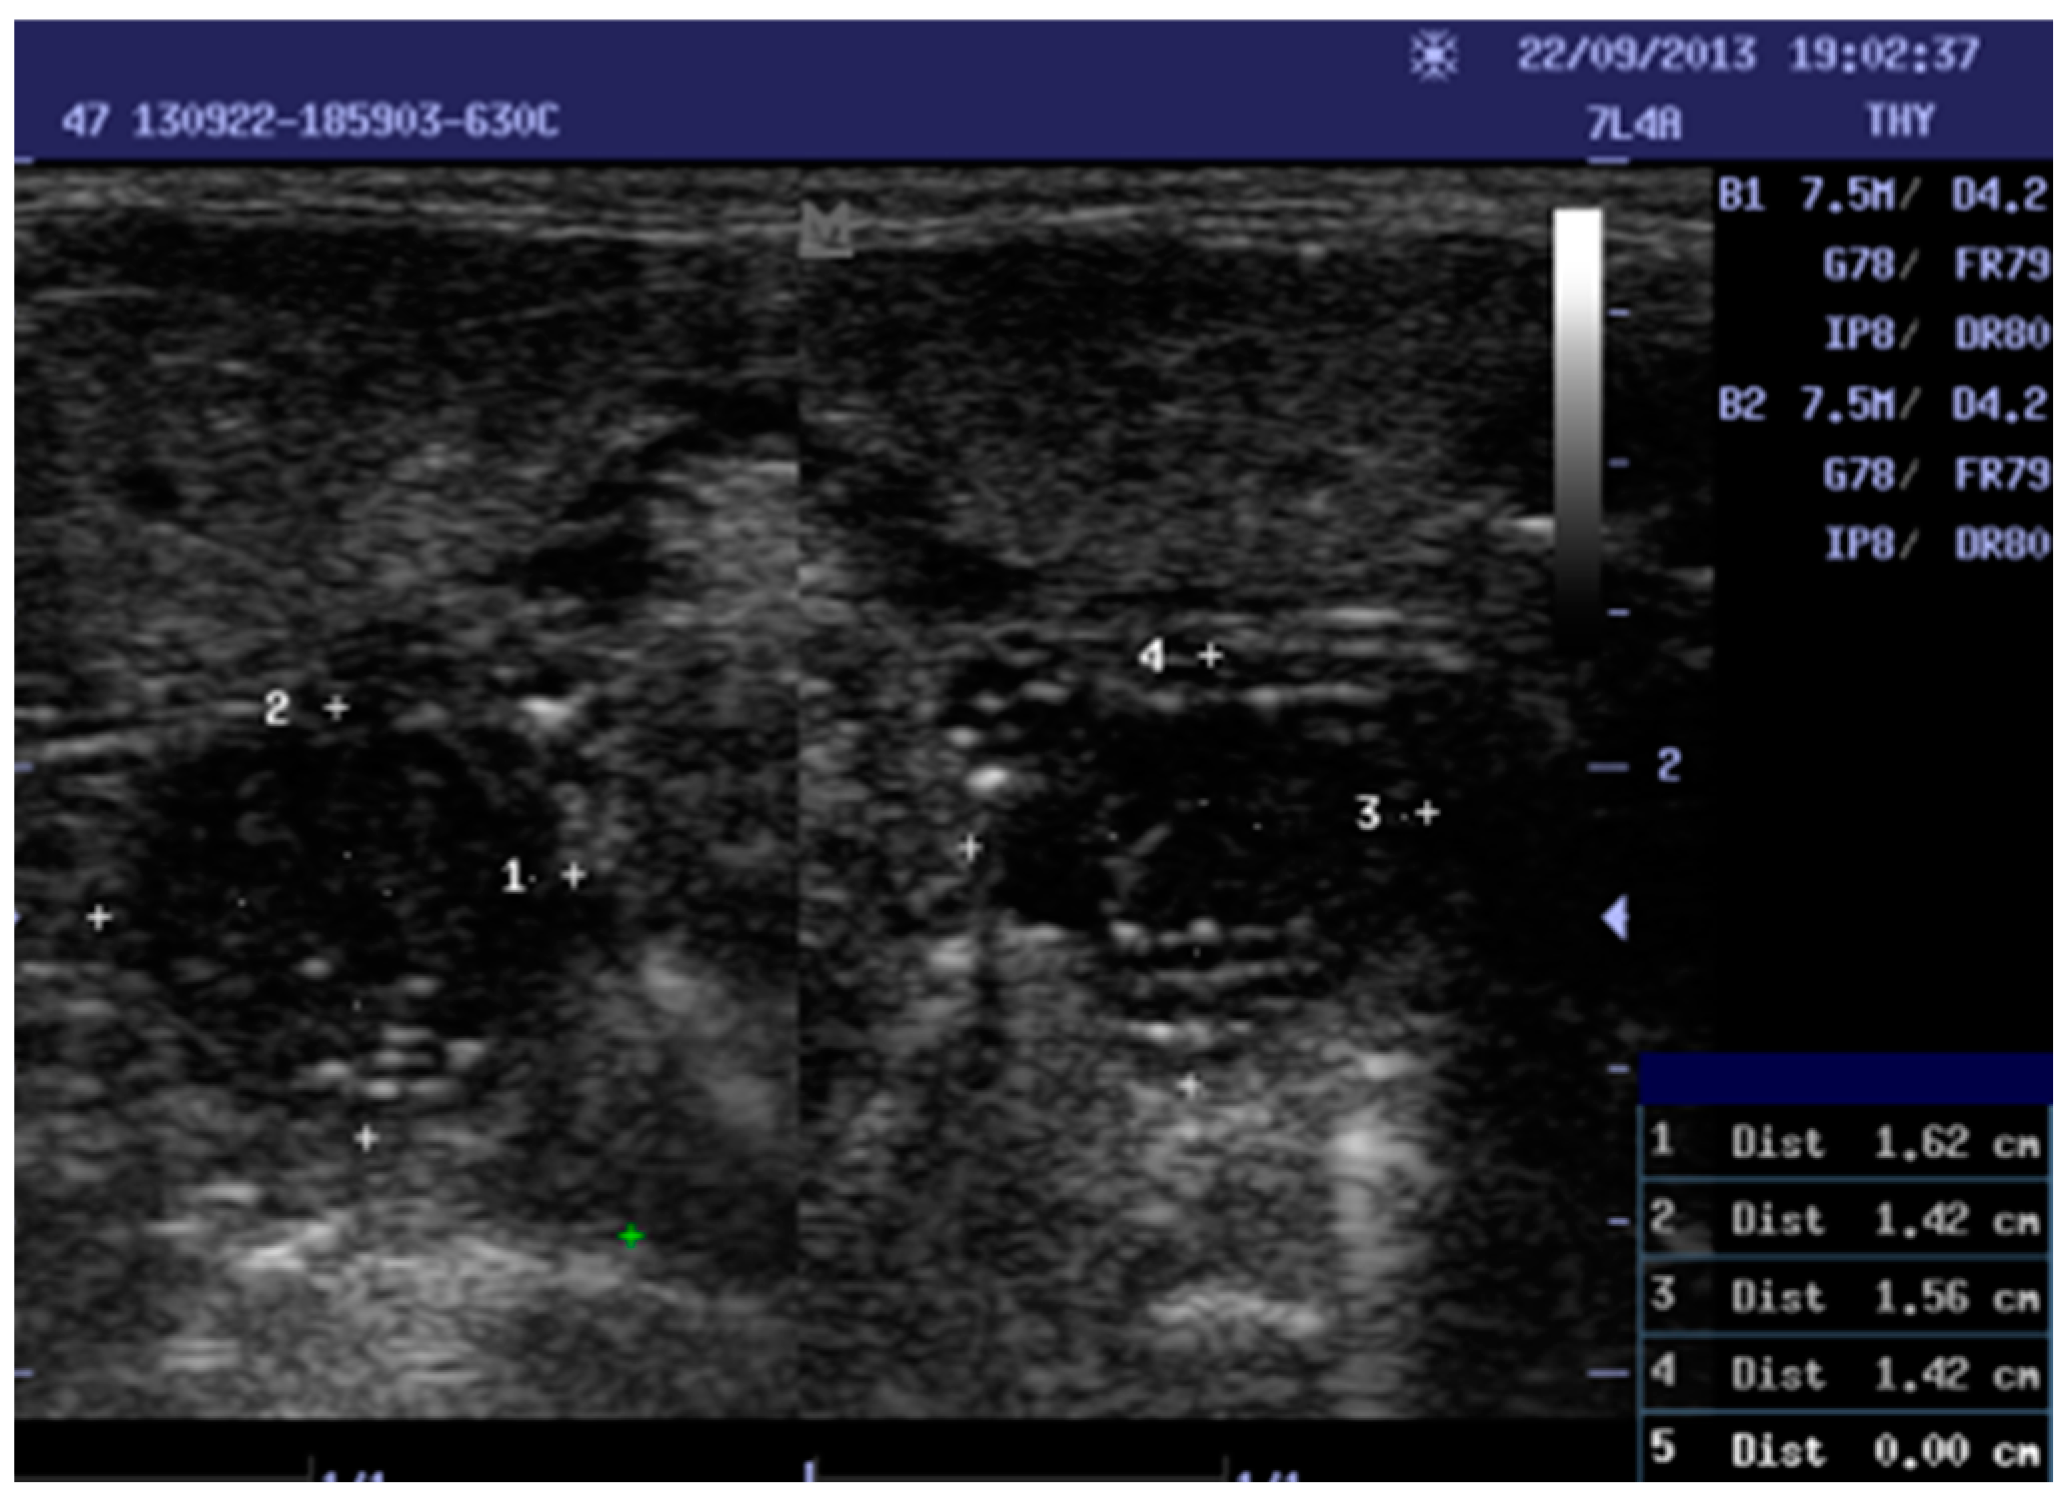

Data were collected by scanning the tonsils of the patients with different portable ultrasound machines (ALOKA SSD-500, MINDARY, and ALOKA UST 5512U), and 5–10 MHz linear ultrasound transducers. Trans-cutaneous sonography was performed. The intraoral exam was avoided because it is commonly used in cases of peritonsillar abscesses. The volunteer was placed in a supine or sitting position with the neck extended during ultrasound scanning. The transducer was placed transversely below the mandibular angle. The tonsil was seen beneath the submandibular gland, above the constrictor muscle, and lateral to the tongue. In normal cases, the tonsil appeared well defined and in a hypoechoic form, with several echogenic reflections attributed to the presence of a little air, and the size of the tonsils was in accordance with the age of the individual. For inflamed tonsils, the palatine tonsils appeared as enlarged with variations in hypoechoic form and unclear differentiation from the proximate tissue. Two measurements in centimeters were taken: height (AP) and width (transverse) for both tonsils (RT and LT; see Figure 1). A data collection sheet was used to record age, history, sonographic measurements, and echogenicity. As the longitudinal and transverse diameters of tonsils are very examiner-dependent, and to ensure inter-rater reliability, two examiners performed all the ultrasound examinations. The percentage agreement reliability test was used to determine the agreement score.

Figure 1.

Shows a ten-year-old female with chronic tonsillitis 1, 3: width, 2, 4: Height. Right tonsil measurements (1.62 × 1.42). Left tonsil measurements (1.56 × 1.42).